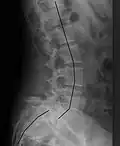

X-ray of the lateral lumbar spine with a grade III anterolisthesis at the L5-S1 level

Spondylolisthesis is graded based upon the degree of slippage of one vertebral body relative to the subsequent adjacent vertebral body.[6] Spondylolisthesis is classified as one of the six major etiologies: degenerative, traumatic, dysplastic, isthmic, pathologic, or post-surgical.[7] Spondylolisthesis most commonly occurs in the lumbar spine, primarily at the L5-S1 level, with the L5 vertebral body anteriorly translating over the S1 vertebral body.[7]

• Grade III: 50–75%